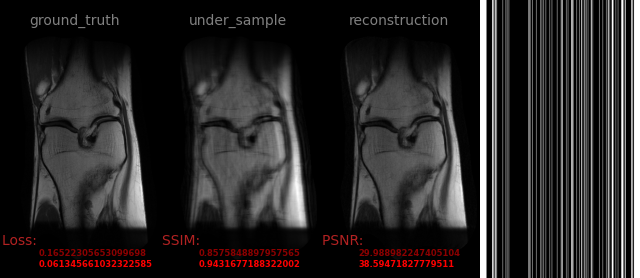

AVS-Net

Image-to-Image

medical

avs_b20